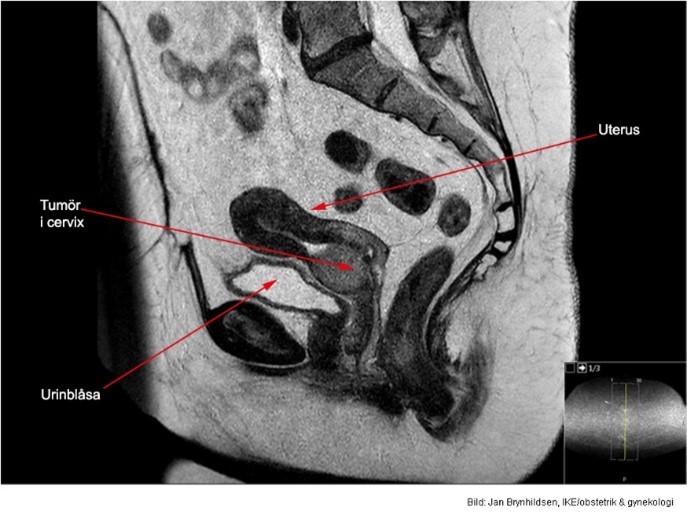

12

Q

Vad visar bilden?

A

Invasivt växande skivepitelcancer.

13

3x4 cm stor cervixtumör utan hållpunkter för spridning.